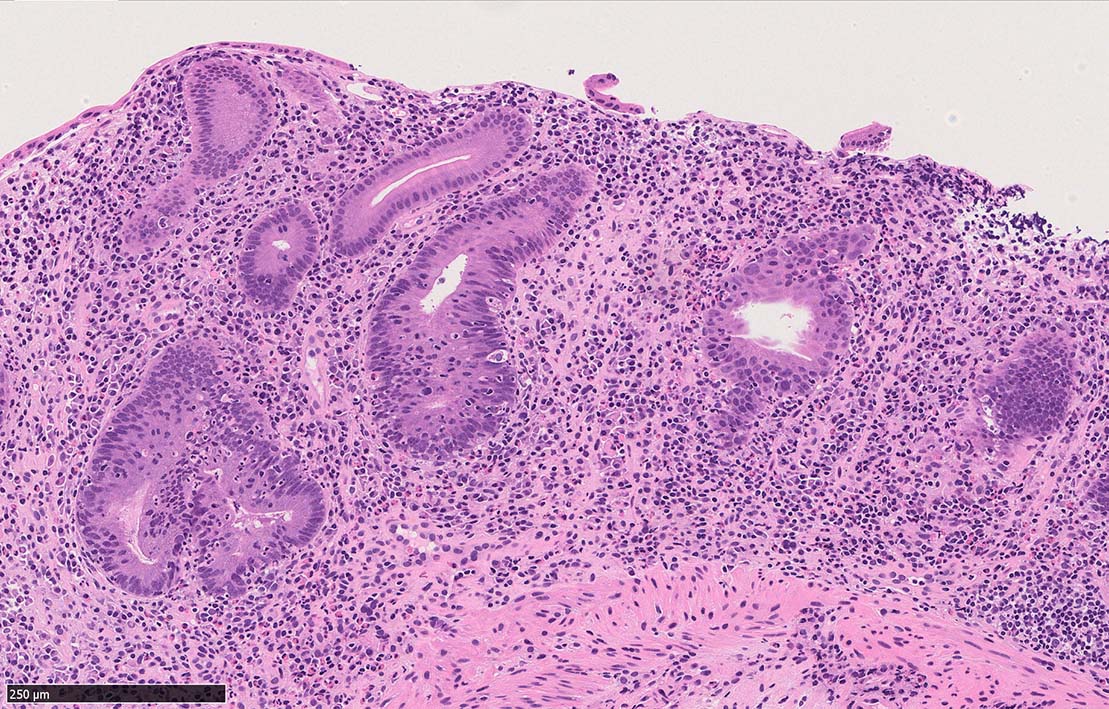

UCのような, crypt abscess, cryptitisが認められる. 特徴的な所見として, apoptosis bodiesの増加が見られる.

陰窩に多数のapoptosis bodiesを認める.